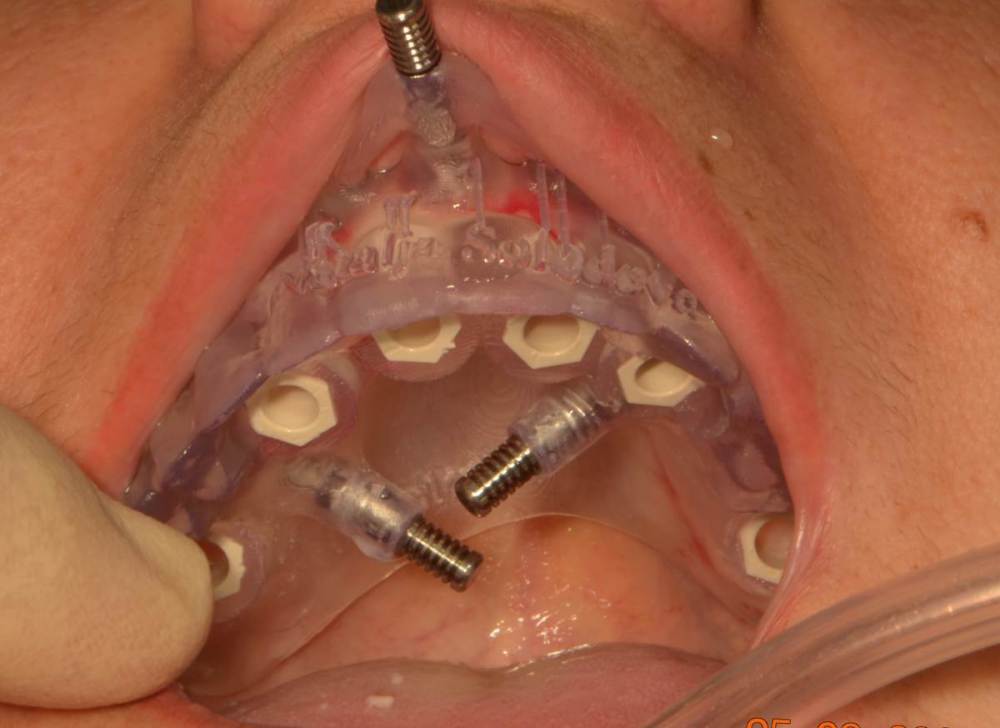

Мартовский Опубликовано 2 октября, 2023 Поделиться Опубликовано 2 октября, 2023 Там везде гной был или только в 14? Лучше зубы использовать для первого шаблона для правильной постановки пинов. А потом удалить и поставить второй шаблон, когда ложе под пины создано, тогда точно промашки не будет. 1 Ссылка на комментарий

Большой Зеленый Опубликовано 3 октября, 2023 Автор Поделиться Опубликовано 3 октября, 2023 Везде воспаление было. зубы оставшиеся точно не помощники были. Ссылка на комментарий